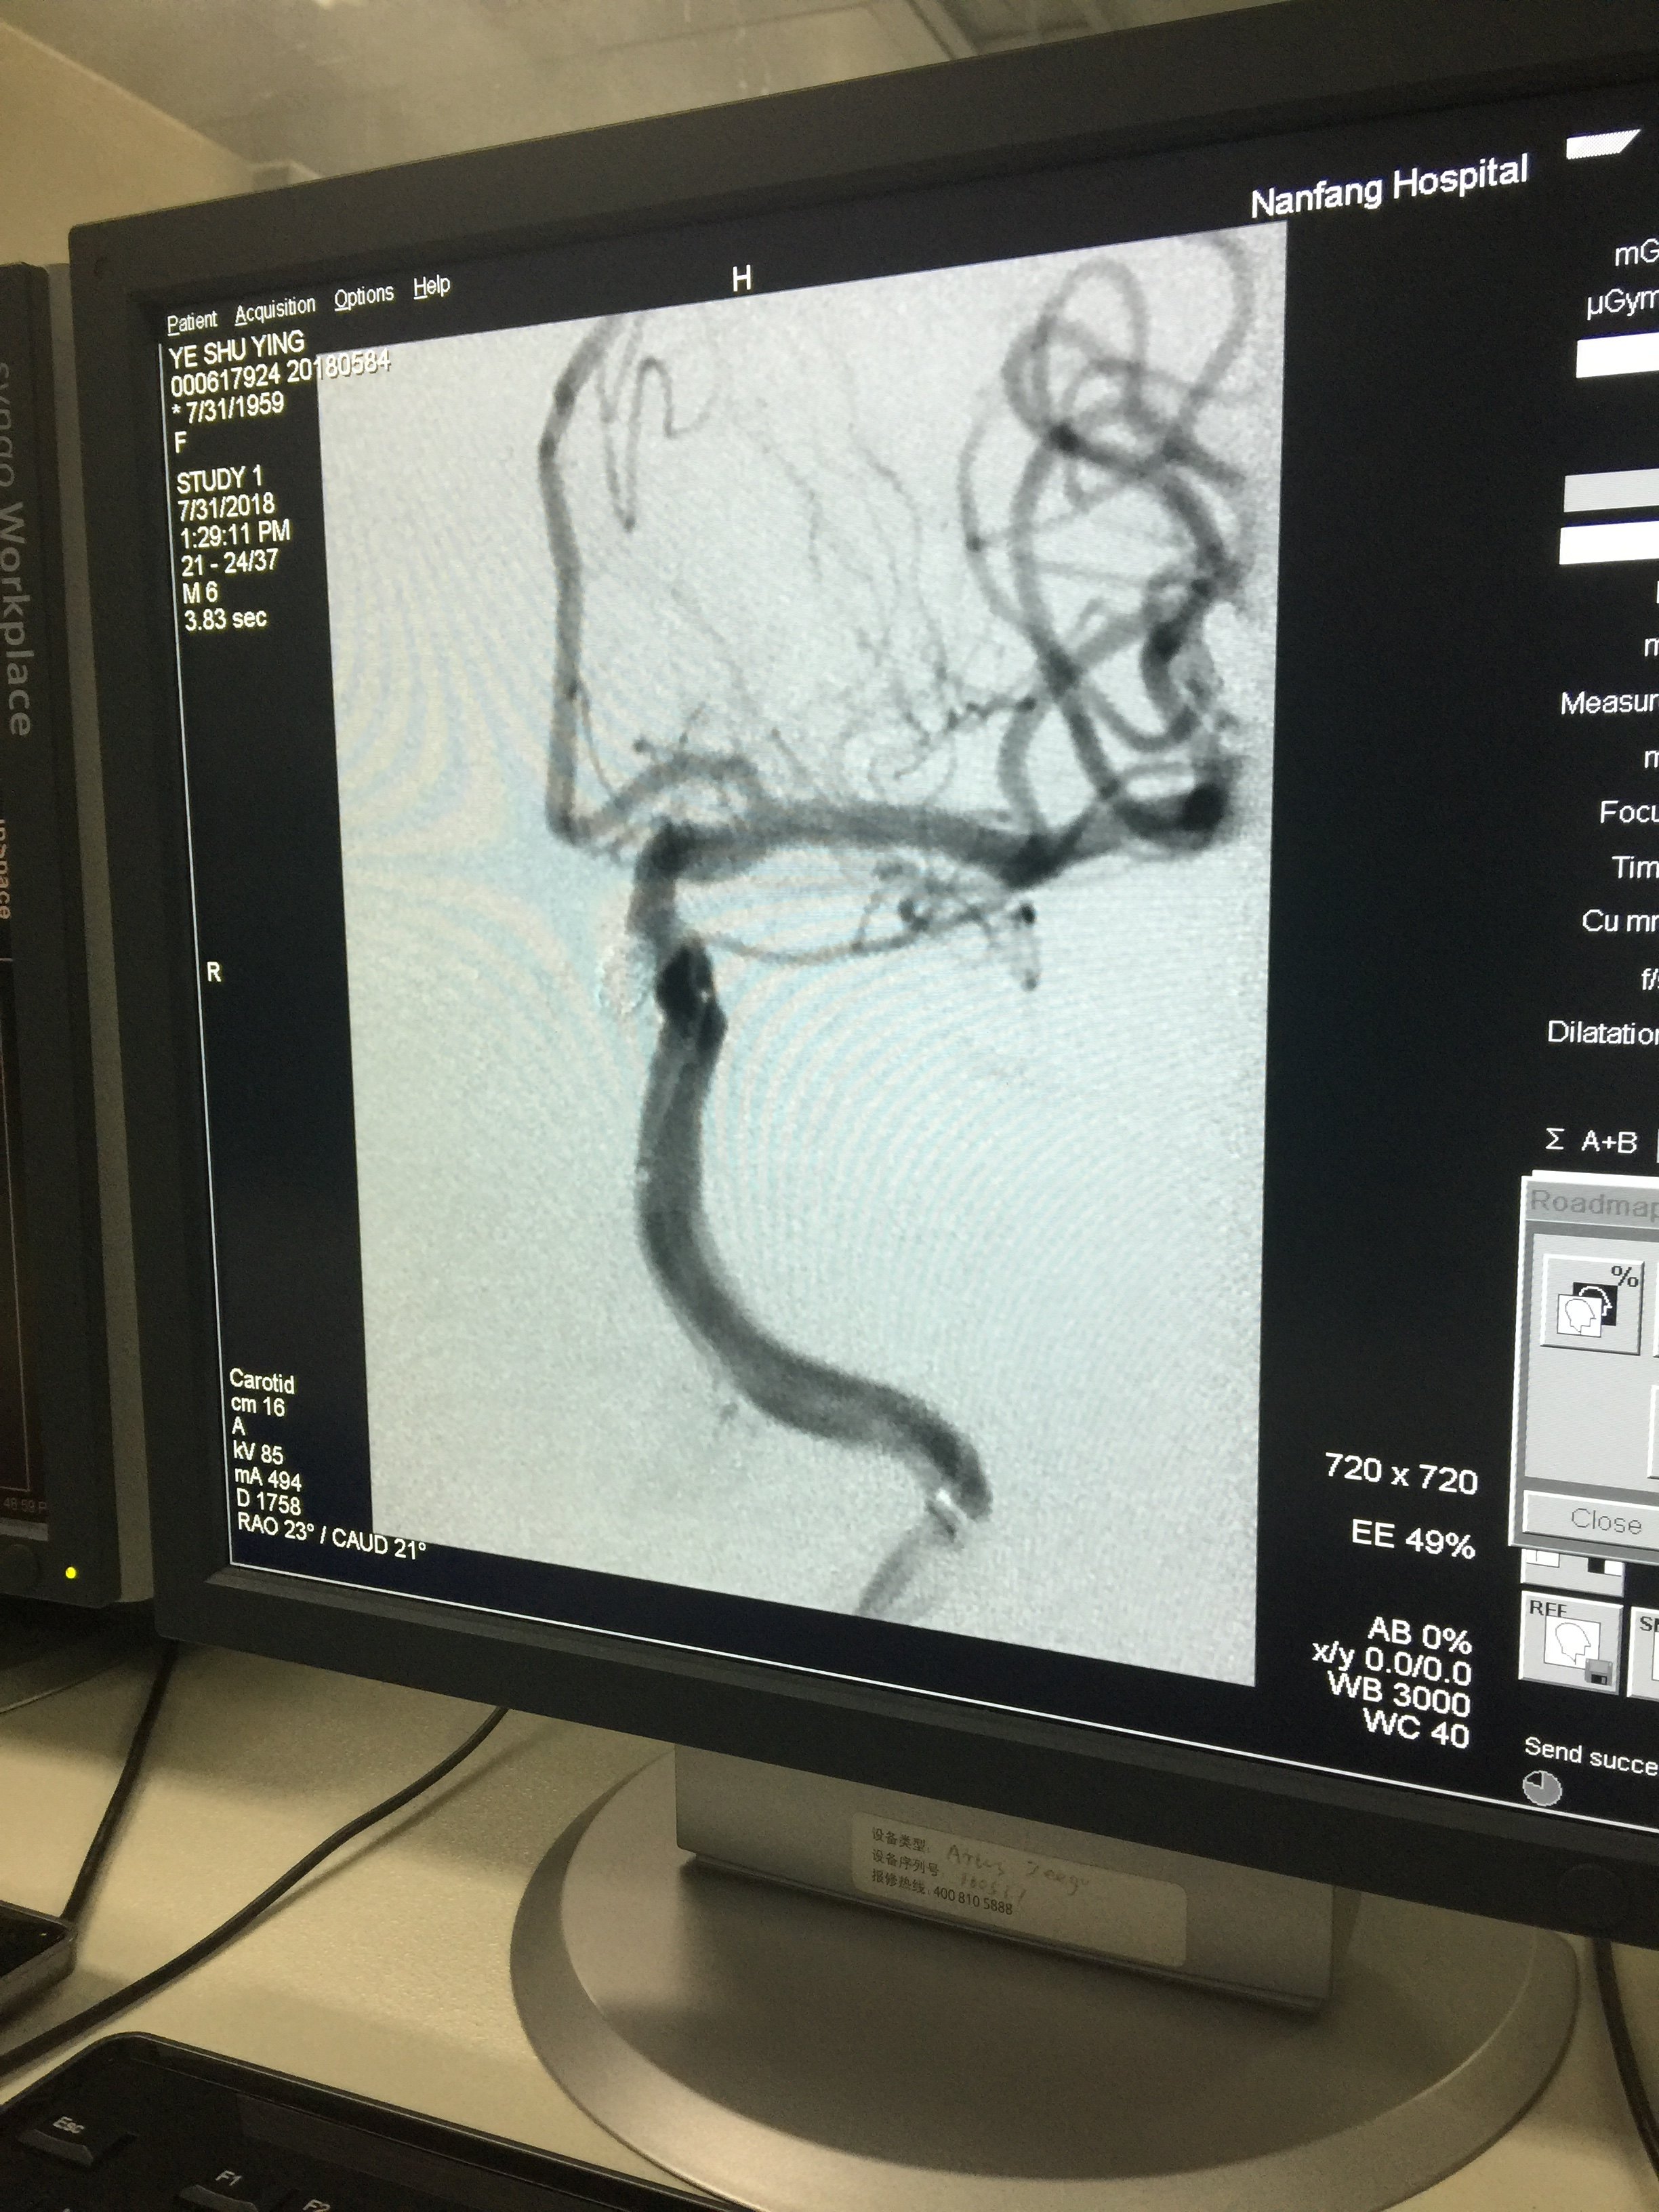

病例一:术前

1534032321.png